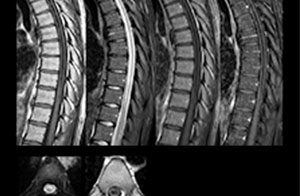

Including mDIXON TSE for robust fat suppression

“We use mDIXON TSE extensively in our spine imaging in the emergency room,” says Dr. Karis. “It’s particularly nice in that it is very robust with regard to susceptibility type of problems that would come up with traditional spectral fat-saturated images; these problems are essentially eliminated with the mDIXON technique. In our ED environment it’s really nice to have the fat-free imaging that goes along with the mDIXON technique.

“For the thoracic and cervical spine routine non-contrast exam, for example, we perform one mDIXON T2 TSE sequence, which provides us with two outputs: the fat-and-water-together T2-weighted images, as well as the water-only sagittal T2-weighted images. And then we also perform an axial gradient echo exam.”